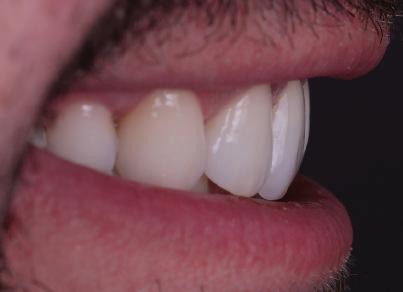

планта бе поставена временна коронка (фиг. 10 и 11), докато бъде изготвена окончателна та. Бе постигнат отличен кра ен резултат. Меките тъка ни около импланта напълно заздравяха, което доприне се за перфектната хармония между бяла и розова естетика (фиг. 12–15).

но

между членовете на екипа и пациента. ЗАКЛЮЧЕНИЕ Случаите на липсващи лате рални резци трябва да бъдат третирани от перспектива та на интердисциплинарна ди агностика и лечение. Употреба та на софтуера ClinCheck има доказани предимства за плани ране, комуникация между кли ницистите и пациента и фи нализиране на лечебния план, като се адресират всички же лания и притеснения на паци ента. Настоящият доклад на клиничен случай доказва, че с помощта на съвременните ме тоди един успешен екип от спе циалисти (ортодонт, консерва тивен зъболекар и хирург) може да се стреми към отлични ре зултати и да постига есте тични и функционални усмив ки без компромиси. Ред. бел.: Статията Treatment of a patient with a congenitally missing lateral incisor using aligners: A case report е пуб ликувана за първи път в сп. aligners–international magazine of aligner orthodontics, бр. 1, издание 1/2022. Библиографията е налична при издателя. За авторите: Д-р Iro Eleftheriadi завършва дентална медицина в Атинския университет, а магистратурата си по медицинска статистика – през 2014 г. в Публичния университет в Атина, Гърция. Специализира ортодонтия и завършва през 2017 г. в Университета в Тел Авив, Израел. Предстои ѝ да защити докторан тура във Факултета по дентална медицина към Университета в Атина, Гърция. Д-р Christodoulos Laspos завършва дентална медицина през 1995 г. в Атинския университет, Гърция, а магистратурата си завършва през 1999 г. във Фа култета по дентална медицина към Университета в Тенеси, Мемфис, САЩ. Печели стипендия и специализира лечение на пациенти с лицево-челюстни малформации в Университета в Тексас, Далас, САЩ, и е сертифициран специалист от Европейския борд на ортодонтите. Той е докторант в Универ ситета в Берн, Швейцария. От 2000 г. д-р Laspos практикува в частната си ортодонтска практика в Лимасол, Кипър. Той е основател и директор на MEDICLEFT, Кипърски център за цепки и лицево-челюстни аномалии, както и директор на фондацията Synergy, която осигурява следдипломно обучение на лекари по дентална медицина. Научен съ трудник е във Факултета по дентална медицина към Европейския университет в Кипър. Д-р Laspos изнася лекции по цял свят по теми като лицево-челюстни мал формации, ортогнатна хирургия, мултидисциплинарен подход и нови технологии в ортодонтията. Той е активен член на Европейското общество на Енгел и прези дент на Европейското ортодонтско общество. Фиг. 12а–c Финални странични (а и c) и фронтална интраорални снимки (b). Фиг. 13а и b Финални оклузални снимки. Фиг. 14 Финална снимка на усмивката отблизо. Фиг. 15 Финална екстраорална снимка на усмивката. Фиг. 16 Финална телерентгенография и цефалометричен анализ. Фиг. 12a Фиг. 13a Фиг. 14 Фиг. 15 Фиг. 16 Фиг. 13b Фиг. 12b Фиг. 12c клиничен случай с алайнери